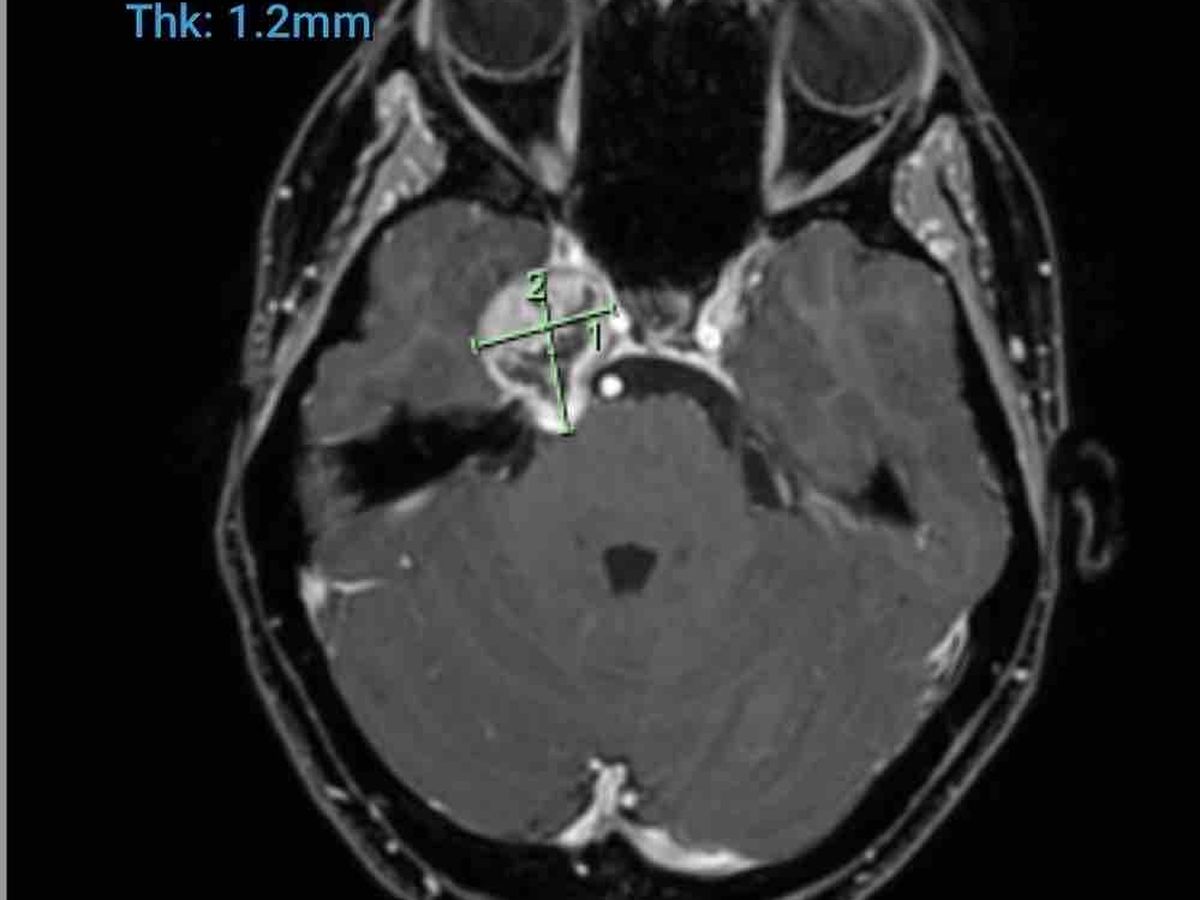

I found out I have Trigeminal Nerve Schwannoma for those who don’t know what this is, it’s a rare skull based Tumour. It’s located on my Trigeminal nerve causing debilitating Headaches, double vision and pins and needles on the right side of my face where my tumour is located. I am thankful & feel like I have won the lotto daily due to the fact that these types of tumours are mainly “benign” meaning they aren’t cancerous. It doesn’t take away how scared I feel, how anxious I am about everything medical, how my anxiety is through the roof, the panic attacks and I know that I have a long way of recovery not only mentally but physically with my road of recovery ahead.